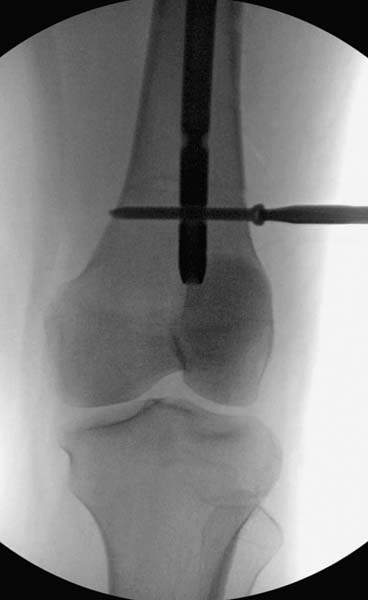

Больная стабильная после хирургических мероприятии и получив добро, приступили к закрытому вправлению таранной кости с укладкой наружного фиксатора. Затем укладка больную на бок и открытый остеосинтез перелома-вывиха головки бедра.

Остеосинтез бедра не стали делать из-за множественных переломов ребер с ушибом грудной клетки и поэтом у закончили фиксацию бедра наружным фиксатором.